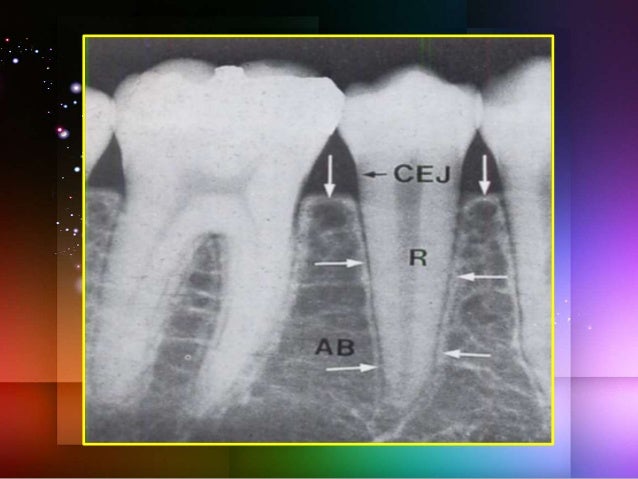

21. 21. The parts of the alveolar bone 1. Alveolar bone proper 2. Supporting alveolar bone o Cortical plates o Spongy bone

22. 22. ALVEOLAR BONE PROPER •Cribriform plate (anatomic term) •Lamina dura (radiographic term) •Bundle bone (histologic term, coined by Stein and Weinmann, 1925) •It is that bone in which the principal fibers of the periodontal ligament are anchored. (Sharpey’s fibers). •This type of bone contains several layers of bone deposited in orientation parallel to the tooth socket wall.

29. 29. INTERDENTAL SEPTA •The interdental septa are bony partitions that separate adjacent alveoli. •Coronally, the inner & outer cortical plates fuse 1mm apical to the Cemento-enamel junction. •The mesiodistal angulation of crest of the interdental septum usually parallels a line drawn between the CEJ of the approximating teeth.

30. 30. The mesiodistal and faciolingual dimensions and shape of the interdental septum are governed by the size and convexity of the crowns of the two approximating teeth, as well as by the position of the teeth in the jaw and their degree of eruption.